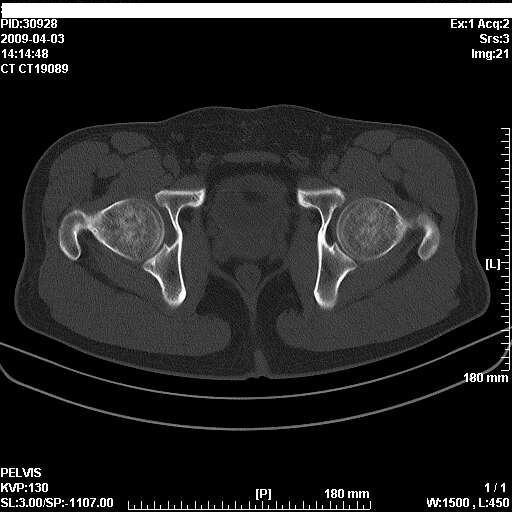

以下是引用随光逐影在2009-4-4 15:13:00的发言:[br]考虑双侧股骨头无菌性坏死;建议行mri检查进一步明确诊断。

以下是引用余辉在2009-4-4 14:22:00的发言:[br]双侧髋关节诸构成骨未见明显异常.必要时mr检查[br]患者症状已有两年,可能要同时从其他方面找原因,个人觉得不排除双侧骶髂关节有问题,建议ct检查